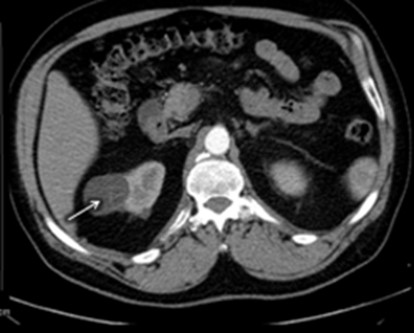

La Categoría II define una lesión con septos finos lisos (< 1mm), calcificaciones lineales continuas o discontinuas o lesiones densas homogéneas en la pared o tabique pero que no experimentan realce a la administración de medios de contraste yodado IV en TC o paramagnéticos en RMI. Su clasificación es de lesión benigna (proteáceos, hemorrágicos, infecciosos).(19, 20) Estos quistes son hiperdensos (40-90 UH < 3cm), mínimamente complicados y no precisan cirugía, deben ser controlados (Anexos 5 y 6).

- Bosniak II: el 10% de los quistes (55 pacientes) fueron catalogados como Bosniak II, correspondientes a quistes benignos. Esta categoría incluyó a 36 pacientes de sexo masculino y 19 de sexo femenino (Anexos 19 y 20).